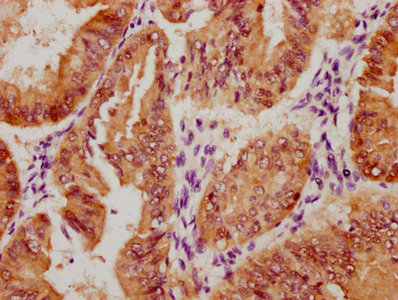

IHC image of CSB-RA169000A0HU diluted at 1:100 and staining in paraffin-embedded human liver cancer performed on a Leica BondTM system. After dewaxing and hydration, antigen retrieval was mediated by high pressure in a citrate buffer (pH 6.0). Section was blocked with 10% normal goat serum 30min at RT. Then primary antibody (1% BSA) was incubated at 4°C overnight. The primary is detected by a Goat anti-rabbit polymer IgG labeled by HRP and visualized using 0.05% DAB.